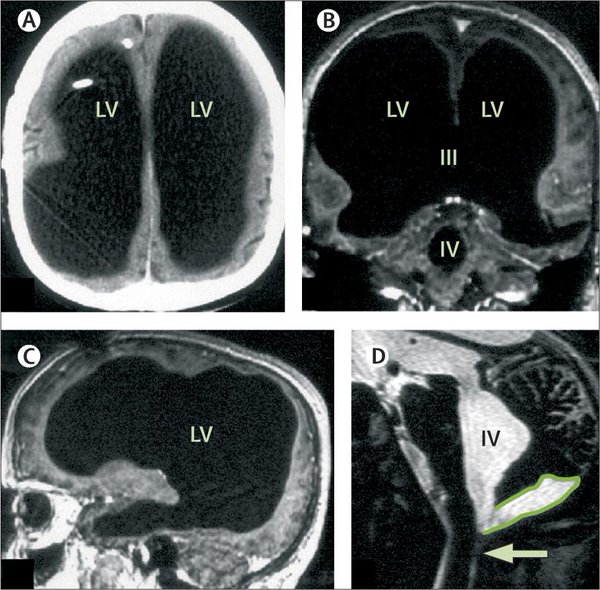

Prowadził normalne życie, miał żonę, dzieci, pracował w urzędzie państwowym. Ale osiem lat temu podczas badania na zupełnie inną przypadłość 52-letni dzisiaj Francuz zadziwił lekarzy. Okazało się, że jego mózg był mniejszy od mózgu zdrowego człowieka o od 50 do nawet 75 proc.

Mimo IQ równego 75 (średnie wynosi 100) mężczyzna prowadził zupełnie normalne życie. To niezwykłe, zważywszy, że na opublikowanym przez pismo medyczne "Lancet" zdjęciu z tomografii jego mózg wyglądał TAK:

[Patrz obrazek poniżej ;)]

- Trudno mi określić stopień redukcji mózgu, nie zmierzyliśmy jego objętości. Ale wygląda to tak, jakby nastąpiła redukcja o ponad 50 proc., nawet do 75 proc. - mówił wówczas dla "New Scientist" neurolog z Uniwersytetu Śródziemnomorskiego w Marsylii Lionel Feuillet.

Ogromny stopień redukcji mózgu

Badania wykazały, że większość czaszki mężczyzny zajmowała komora wypełniona płynem. Tkanka mózgowa zajmowała o wiele mniej miejsca - jak widać na zdjęciu z prawej. Jak się okazało, jako dziecko Francuz przeżył skomplikowany zabieg - wszczepienia przewodu do czaszki w celu usunięcia wodogłowia. Narzędzie usunięto, gdy miał 14 lat. Ale w kolejnych latach w jego głowie zaszły bardzo dziwne zmiany - powiększenie komór z płynem mózgowo-rdzeniowym, które z reguły zajmują niewielką objętość czaszki. W efekcie pozostałe części mózgu - odpowiedzialne m.in. za ruch, wzrok, słuch czy funkcje emocjonalne i kognitywne - zostały radykalnie zmniejszone.

Pacjent nie był upośledzony umysłowo

Ale mimo tak drastycznej redukcji mózgu Francuz nie jest upośledzony umysłowo, nie przeszkodziło mu to też pracować jako urzędnik państwowy. Jak to możliwe? Max Muenke - niepowiązany z zespołem badaczy specjalista od defektów mózgu - stwierdził, że zmiany, z którymi został skonfrontowany w bardzo młodym wieku mózg pechowego Francuza, następowały powoli - i dlatego cały narząd zdołał się przystosować do nietypowej sytuacji. Inne obszary mózgu przejęły funkcję tych, których rozwój został ograniczony.